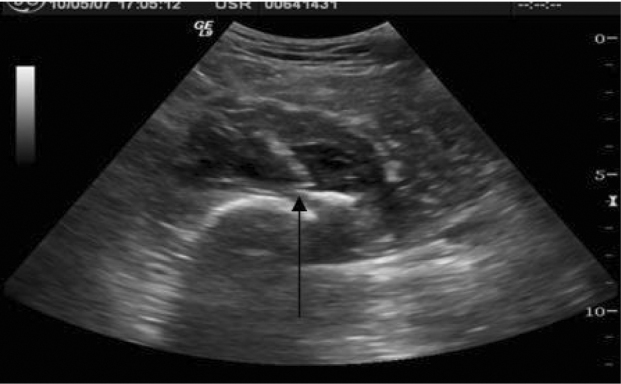

The patient was admitted and on the following day ultrasound guided drainage of the abscess with retrieval of the loose body was attempted. The patient was placed in the supine position on the examination table and scout scans were obtained. A linear, dense loose body measuring approximately 1 cm in length was seen within the fluid collection (Fig. 3).

Figure 3.

Axial Sonogram of the medial thigh shows a hyperechoic, loose body within the infero-medial aspect of a hypoechoic fluid collection.